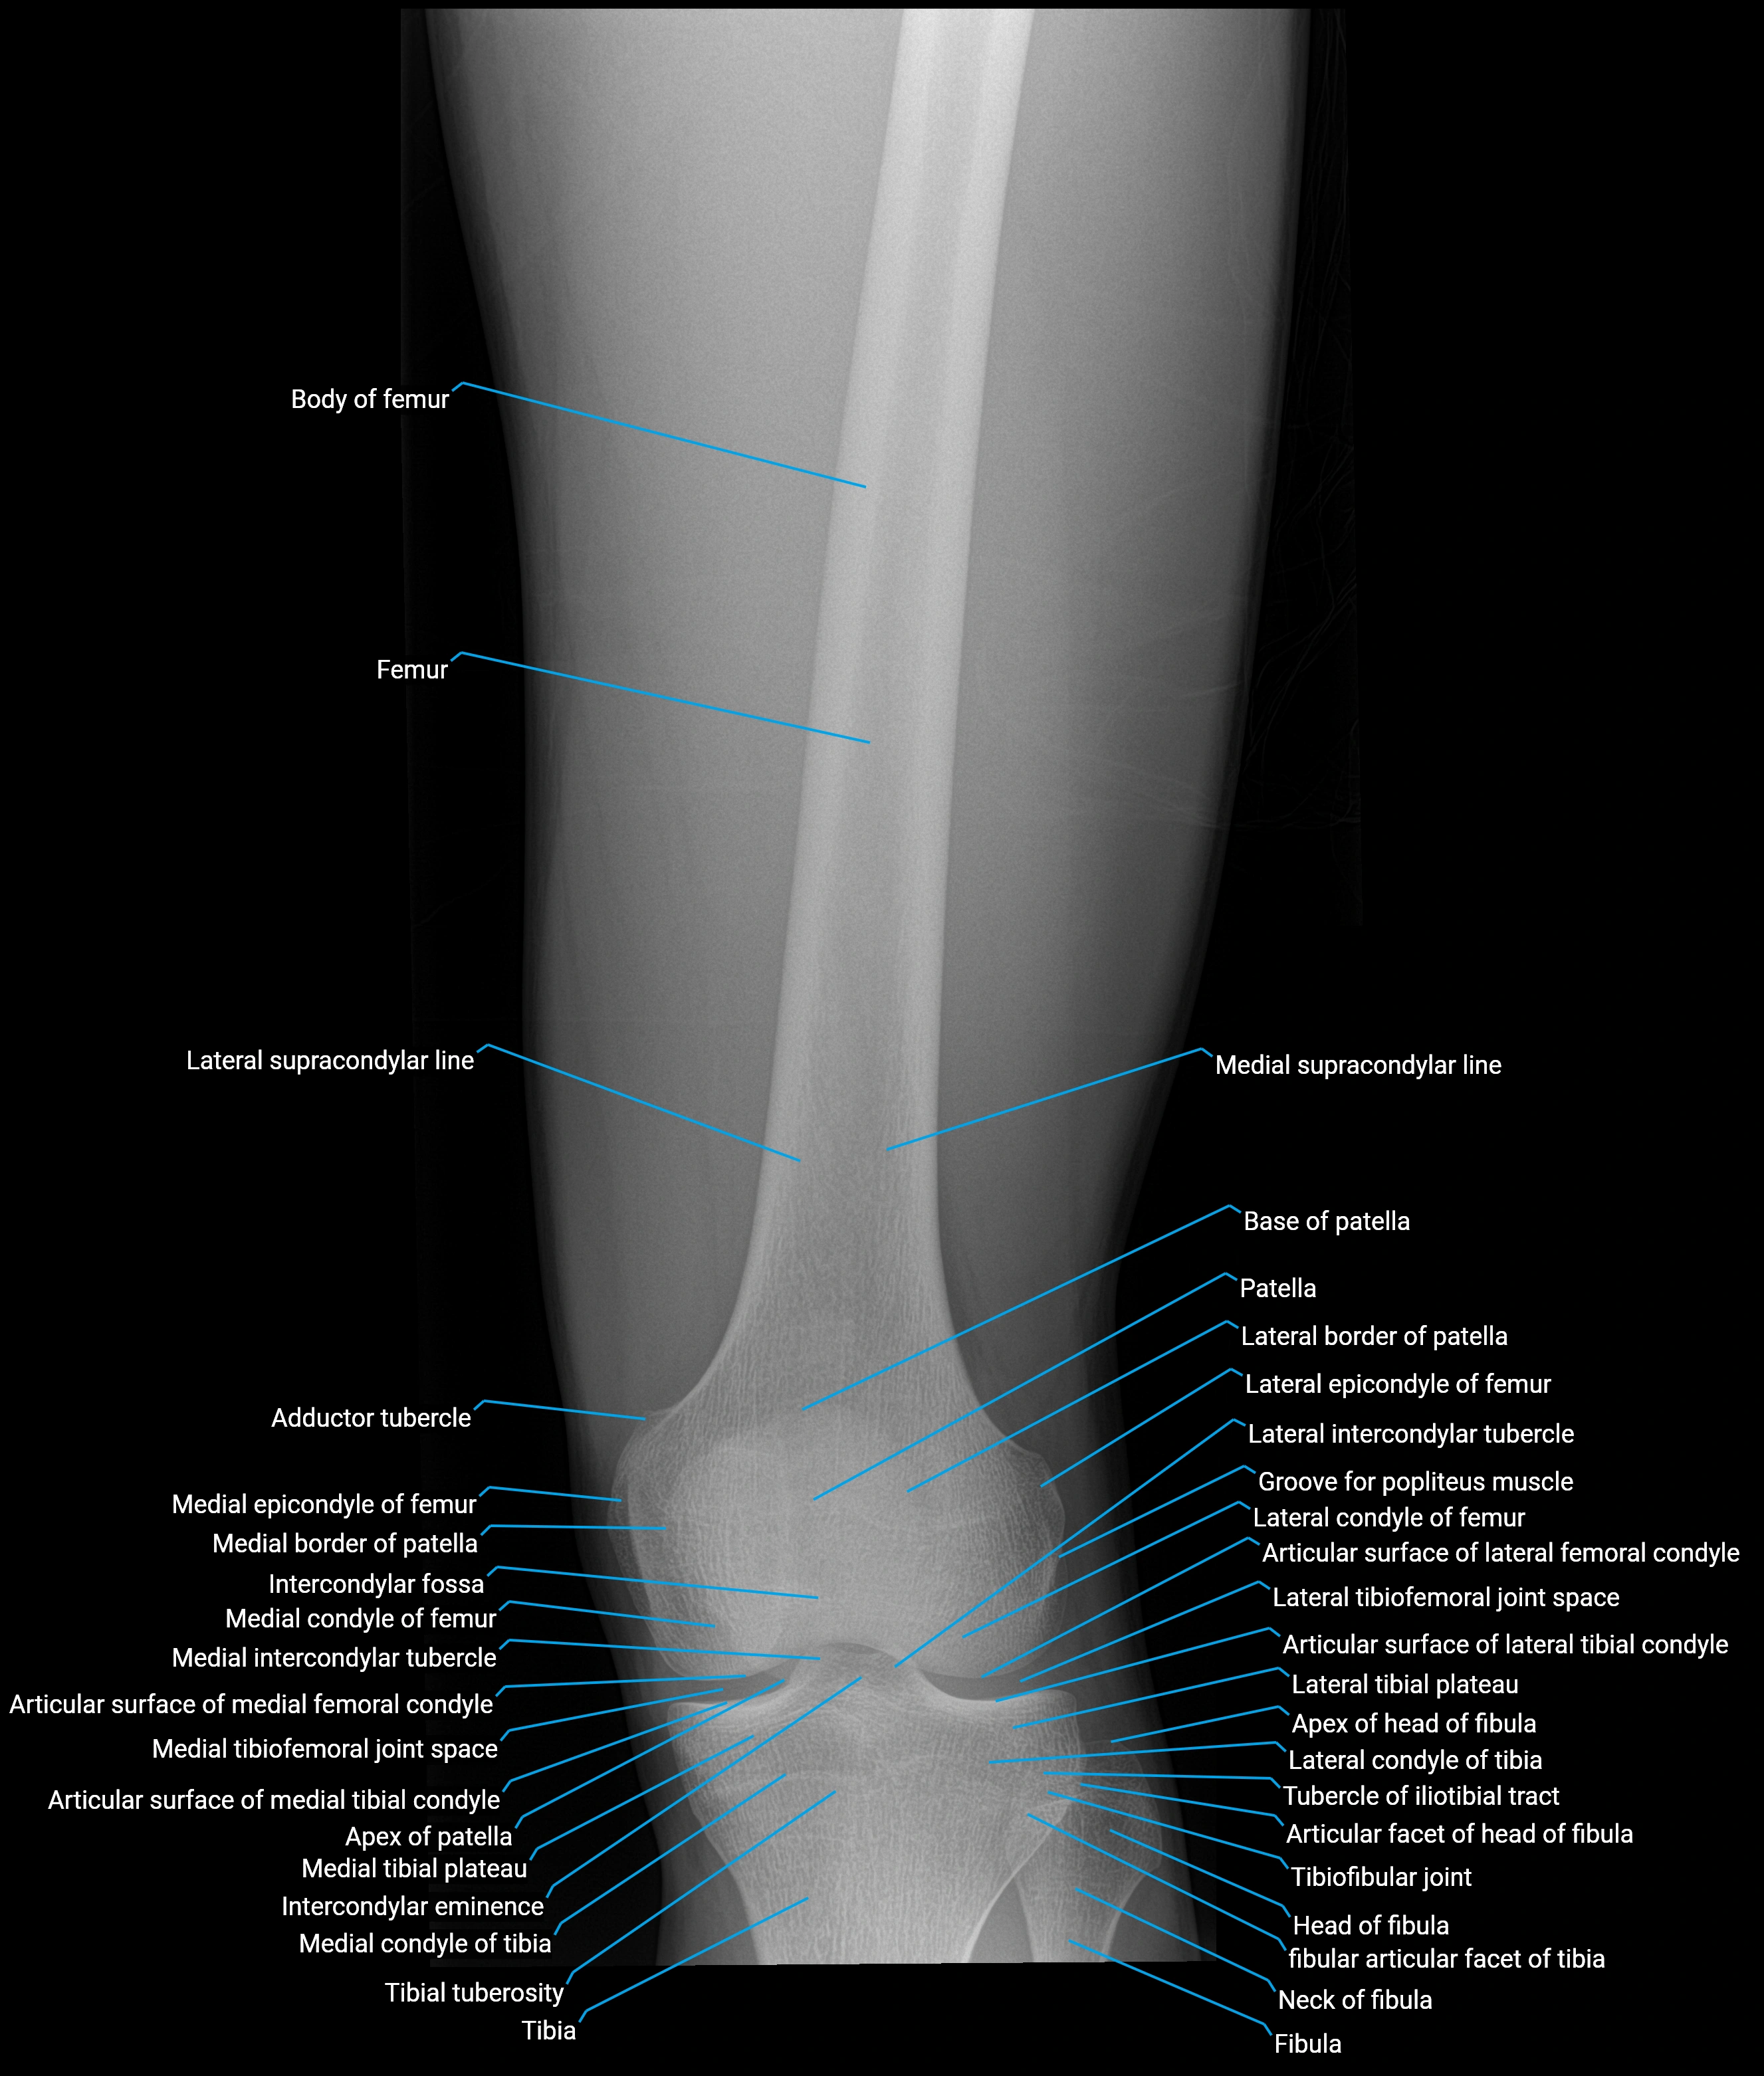

Structure and Relations

• Superior and anterior labrum: thickest portions, stabilizing against anterior dislocation

• Inferior labrum: blends with the transverse acetabular ligament bridging the acetabular notch

• Relations:

• Medial: acetabular articular cartilage

• Lateral: hip joint capsule

• Inferior: transverse acetabular ligament

• Superior: femoral head